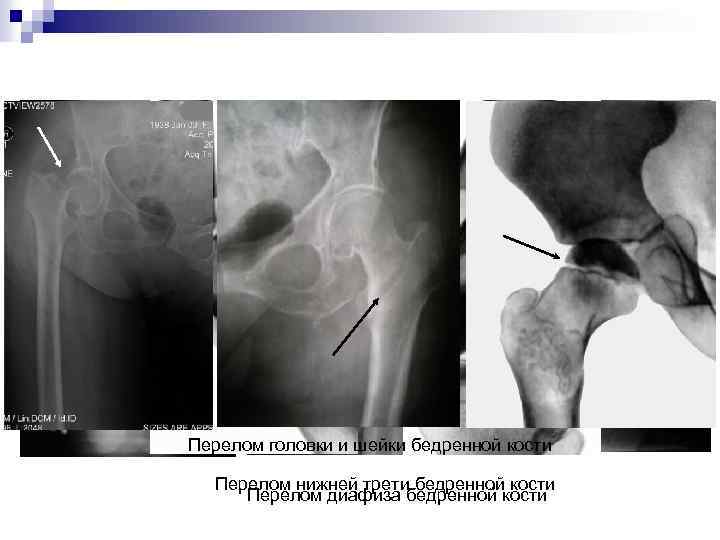

Перелом бедренной кости n n n Перелом бедренной кости происходит под действием прямого удара в область бедра, при падении на твердый предмет, при действии непрямой силы – сгибания, скручивания. Выделяют переломы : верхнего конца бедренной кости: - внутрисуставными (капитальный, субкапитальный, трансцервикальный, базисцервикальный) - внесуставными (вертельные, межвертельные и чрезвертельные) средней части (диафиза кости): - поперечные - косые - винтообразные - оскольчатые переломы нижнего конца бедренной кости, к которым относятся переломы мыщелков бедра.

Перелом головки и шейки бедренной кости Перелом нижней трети бедренной кости Перелом диафиза бедренной кости